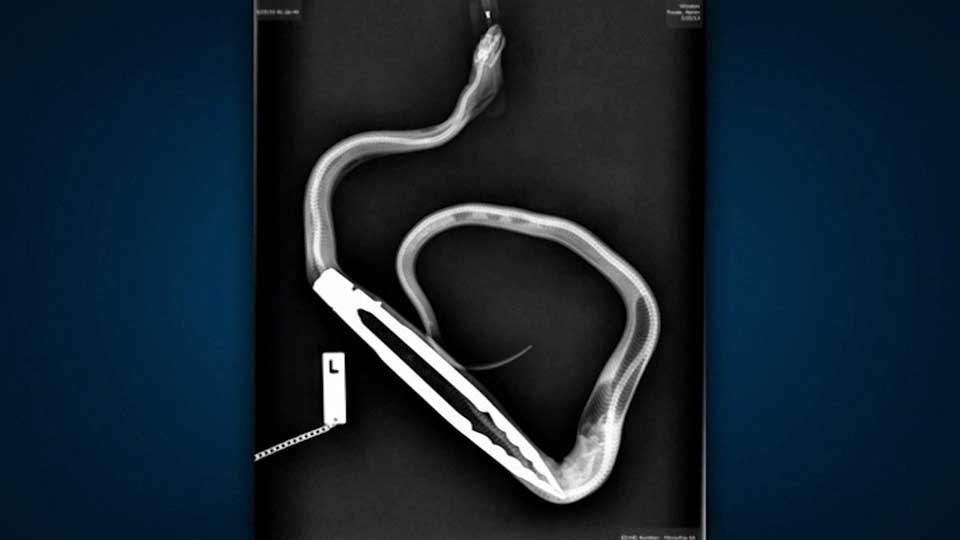

ADELAIDE – A python has undergone surgery in Australia to remove a pair of barbecue tongs which the reptile swallowed, local media reported.

“I can remember doctor Oliver saying to me ‘now are you sure the tongs are in his belly?'”, Rouse told Channel 9. “And I said, unequivocally, ‘yes, you can read the brand name of the tongs through his skin.”

X-rays were ordered to confirm and surgery was performed taking Funnell and his team about 20 minutes to remove the metal.